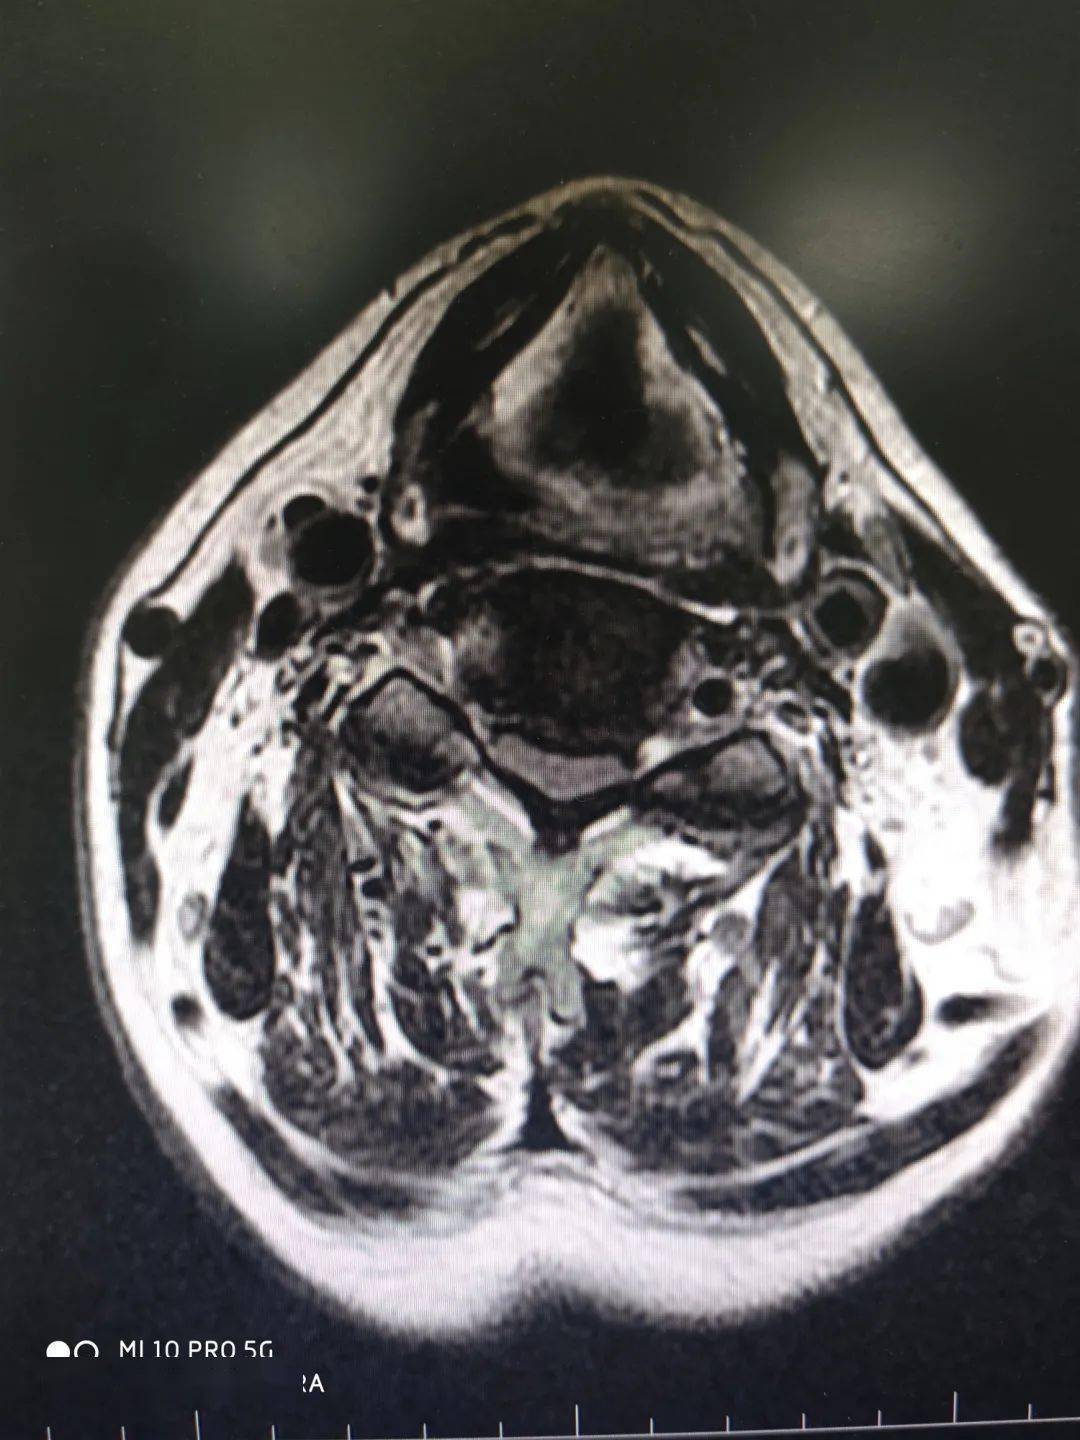

正常颈椎核磁图片

正常颈椎核磁图片,颈椎核磁图片正常

颈椎mri图像

颈椎核磁图片正常

颈椎核磁图片

颈椎核磁共振图片图解

颈椎核磁图片怎么看

颈椎核磁正常

颈椎核磁图谱解析

颈椎磁共振图片详解

教学看会颈椎核磁图

颈椎的核磁共振的图解

颈椎核磁

颈椎核磁解剖

怎样看懂颈椎磁共振图

颈椎核磁共振报告

颈椎核磁共振报告单